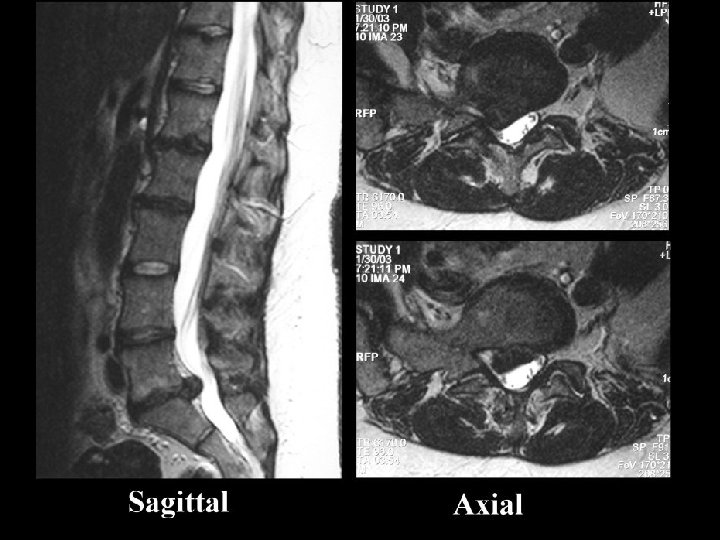

Radiculopathy: Etiology • Structural – Disk – Spondylosis – Tumor – Abscess – Hematoma